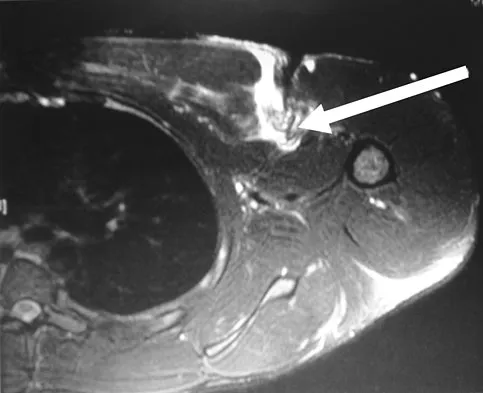

A 23-year-old man reports pain on the superior aspect of his right shoulder with repetitive overhead activities and when lying on his right side. Figure 29 shows an axial MRI scan. What is the most likely diagnosis based on the MRI findings?